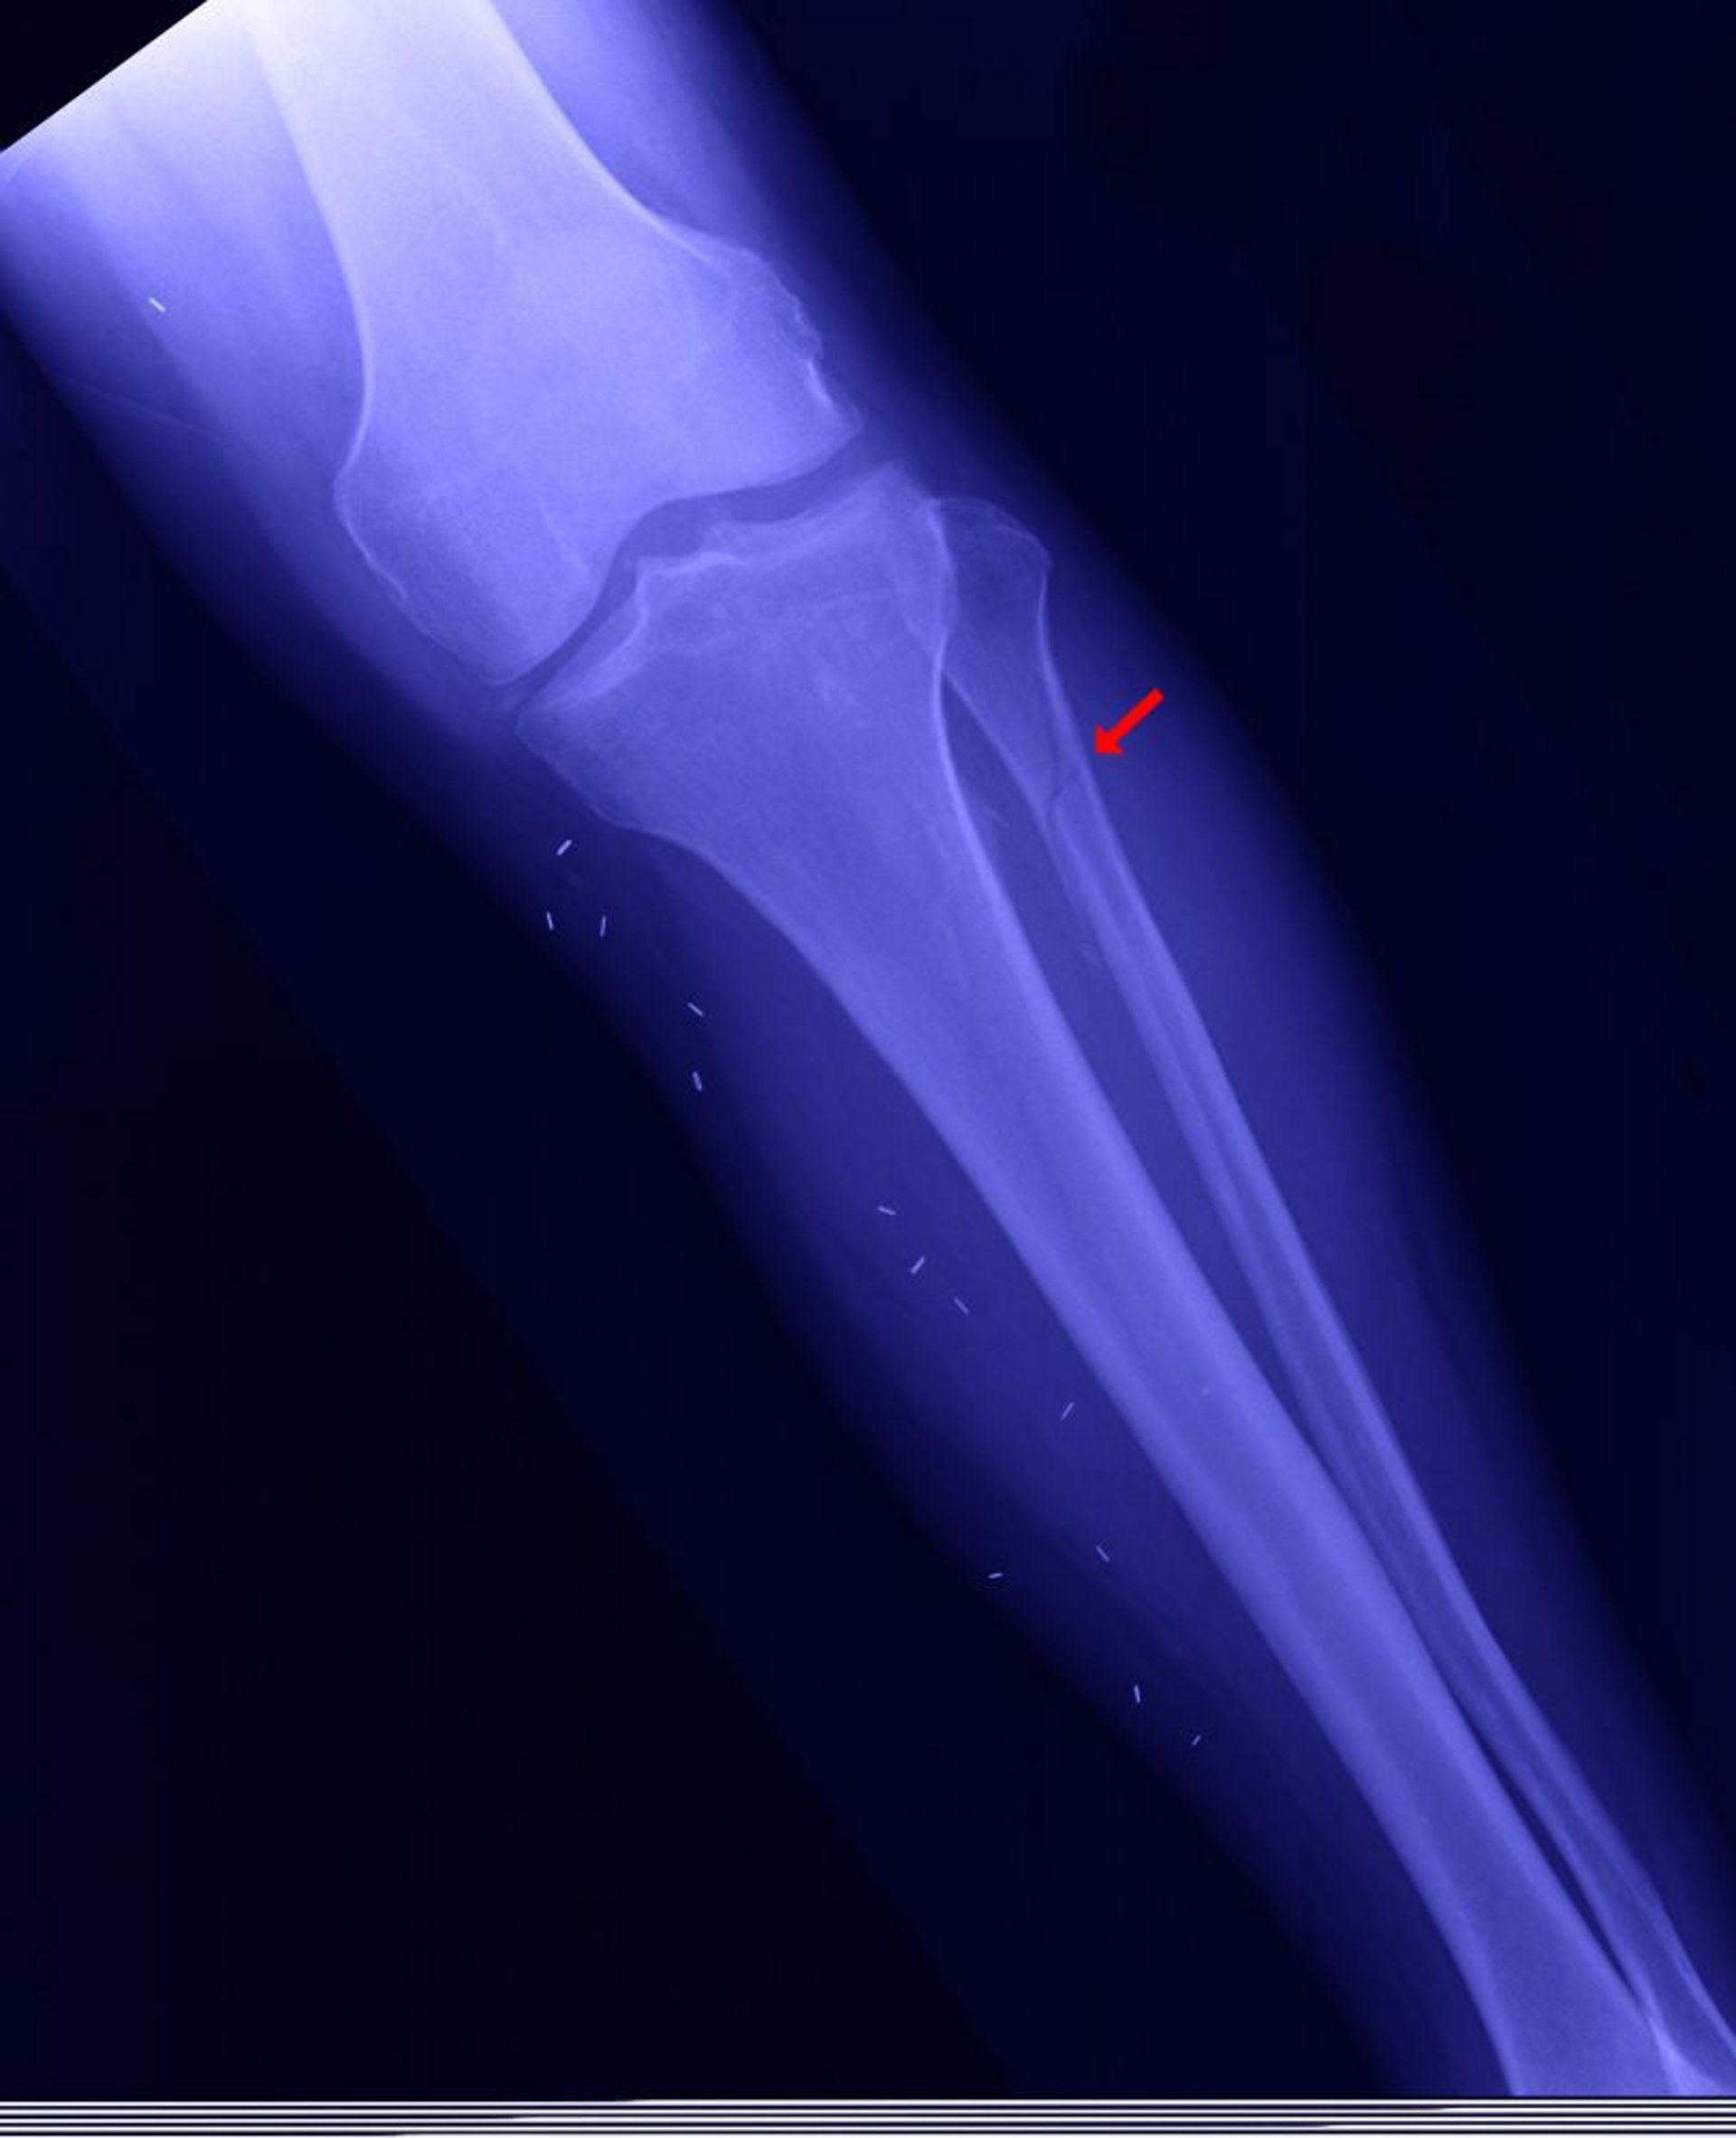

Frattura prossimale del perone

Il perone prossimale si può fratturare (questa frattura è chiamata di "Maisonneuve", mostrata qui) quando il malleolo mediale è fratturato, il mortaio della caviglia (l'articolazione tra la tibia e l'astragalo) è aperto, e il perone distale non è fratturato.